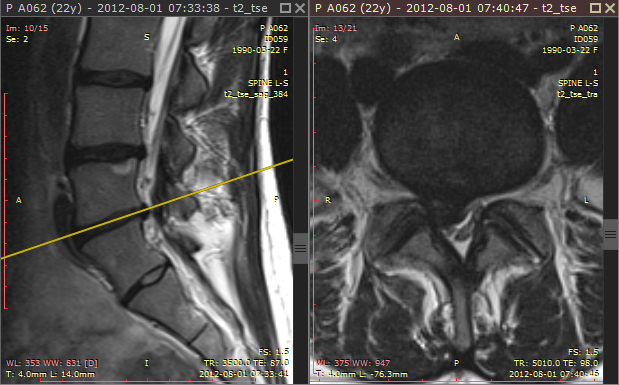

浏览不同图像平面的序列时(例如磁共振检查),交叉参考线可帮助更好地关联解剖结构。它们显示为黄色线条,标记各图像平面的交线位置。

交叉参考线示例 1

交叉参考线始终在非活动面板(灰色标题栏)中显示,作为活动面板(棕色标题栏)图像的参考。